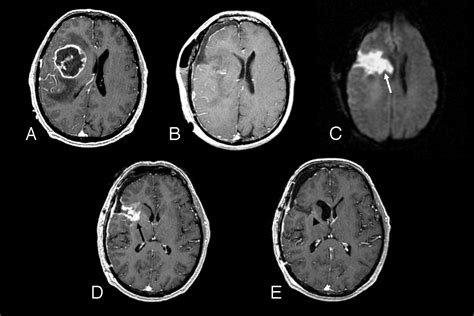

• Diffusion-Weighted Imaging (DWI): Measures the movement of water molecules to help distinguish between different types of tumors or identify abscesses.

• Magnetic Resonance Spectroscopy (MRS): Analyzes the chemical composition of the tissue, helping to distinguish tumor tissue from radiation necrosis.

• Perfusion Imaging: Maps the blood flow volume within the tumor, which can help indicate how aggressive a tumor might be.

These advanced tools provide the neurosurgeon with a "map" of the brain, identifying functional areas—such as speech or motor cortex—that need to be avoided during surgery. This level of precision is what makes the modern Brain Neoplasm MRI an indispensable tool in neuro-oncology.

Interpreting the Results